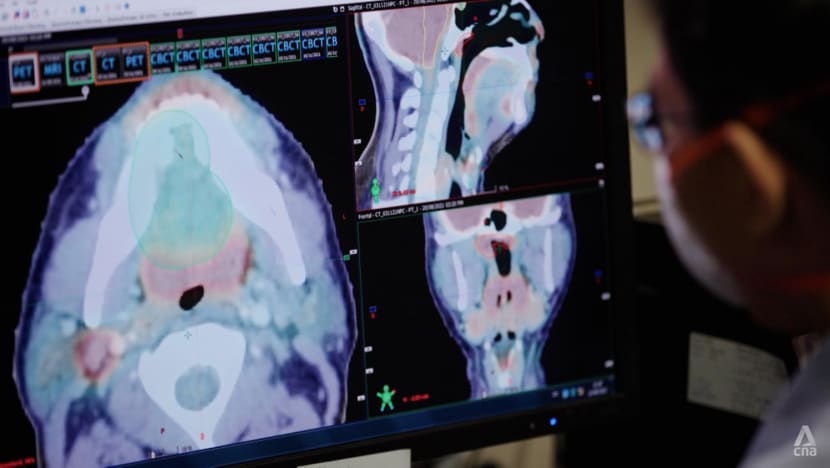

Before treatment, radiation oncologists use CT scans to design the direction and strength of radiation beams to treat the tumour while avoiding healthy organs.

To target tumours, a radiation oncologist would first have to assess the suitability of a patient, as well as both the type and technique of radiotherapy.